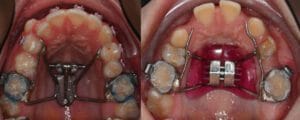

1-The smile, because upper jaw narrowness will lead to “Black corridors” on the corner of the mouth during smiling, as we see in the following case, and we will notice a great improvement on the smile and the incredible increase of the white color of the teeth, during smiling after we did expansion of upper jaw transversely.

Expanding upper jaw may lead to the appearance of a gap between upper central anterior teeth. The appearance of this gap is something good and indicate to a successful upper jaw expansion, this space may remain temporarily for some time and gradually it will be closed either spontaneously or through orthodontic braces.

There are several designs for this appliance , most of them work in the same concept, but differ in small details